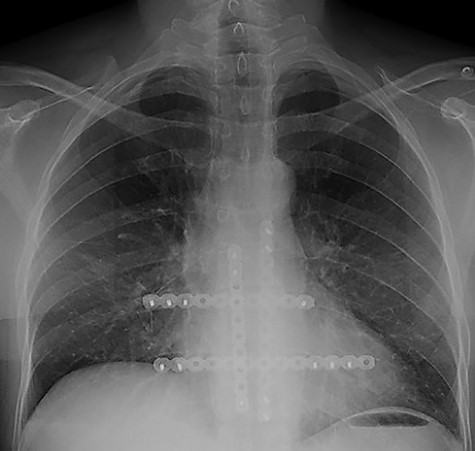

The second case at our institution was a 52-year-old woman with a history of left breast carcinoma treated for which she had undergone left wide local excision and sentinel node biopsy. Due to uncertainty regarding margins, she required a re-resection of her left breast tissue. She completed adjuvant radiotherapy and received maintenance hormonal therapy. She presented 8 months following her radiotherapy with sternal pain and positron emission tomography–computed tomography (PET–CT) imaging demonstrated localized uptake within the sternum (Fig. 3). Biopsy demonstrated proven recurrence of metastatic breast cancer. She was seen in clinic and counselled for partial sternectomy and reconstruction. She underwent partial sternectomy and underwent reconstruction with Synthes® plates. Her post-operative recovery was unremarkable. Post-operative histology was consistent with metastatic breast carcinoma, which was completely excised. The patient made an uncomplicated recovery and was seen in the outpatient clinic with a satisfactory post-operative chest radiograph (Fig. 4).